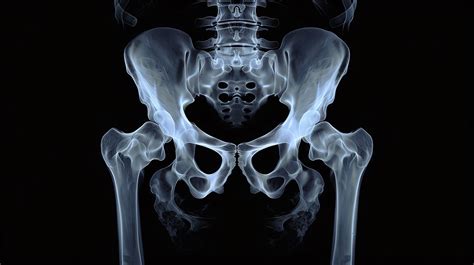

To understand the symptoms, it is helpful to understand the mechanics of the condition. Your hip is a ball-and-socket joint. Ideally, the ball (the top of the thigh bone, or femur) fits perfectly into the socket (a cup-shaped part of the pelvis). In individuals with hip impingement, either the ball is not perfectly round, the socket is too deep or incorrectly oriented, or a combination of both.

This anatomical discrepancy causes the bones to rub against each other during movement rather than gliding smoothly. Over time, this friction damages the labrum—the soft tissue ring that cushions the hip joint—leading to pain, stiffness, and restricted range of motion. Because these structural issues are often present from birth or develop during growth, Hip Impingement Symptoms may not appear until the person engages in activities that stress the joint, such as sports or prolonged sitting.

Imaging studies are essential for a confirmed diagnosis. An X-ray is usually the first step to visualize the bone structure and identify any bony prominences (cam or pincer deformities). In some cases, an MRI may be ordered to assess the condition of the labrum and surrounding soft tissues, ruling out tears that may require specialized treatment.